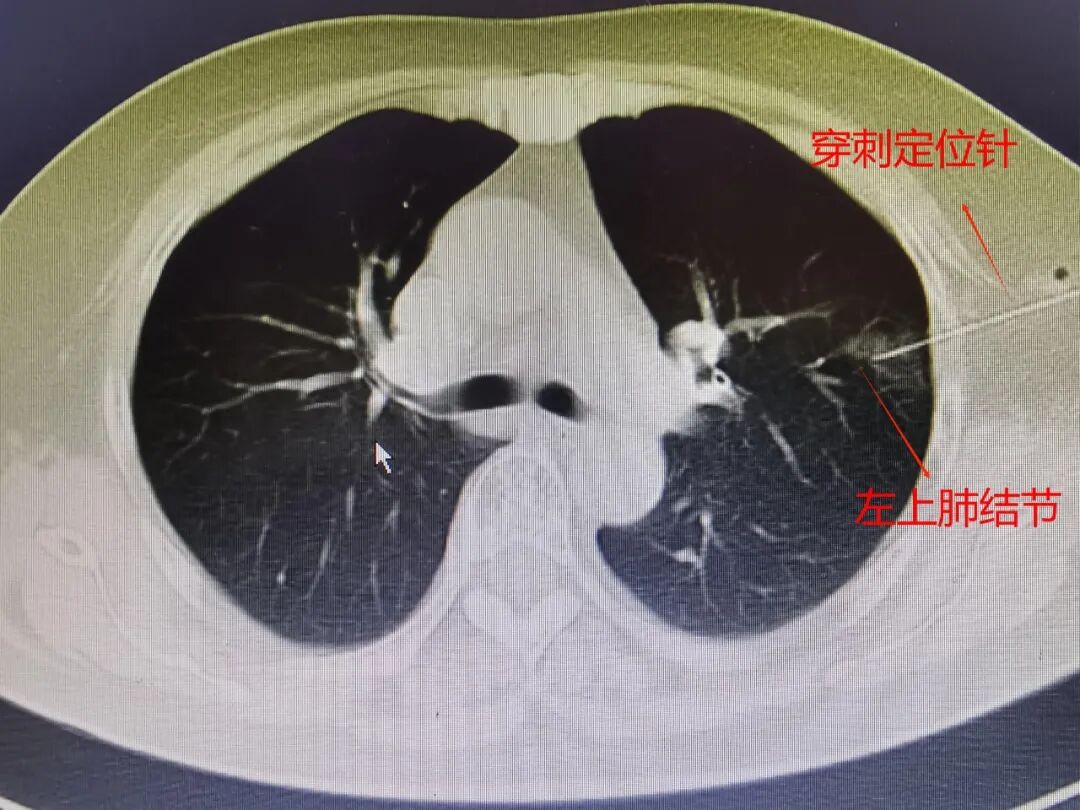

手術(shù)當天一大早,胸外科醫(yī)師護送趙阿婆來到CT室。在CT引導下,采取局部麻醉,相對比較表淺的右上肺結(jié)節(jié)使用穿刺針刺入肺表面后注射亞甲藍染色標記,左上肺偏深稍大的結(jié)節(jié)使用肺穿刺定位針,將定位針尖端勾住結(jié)節(jié)周圍肺組織。